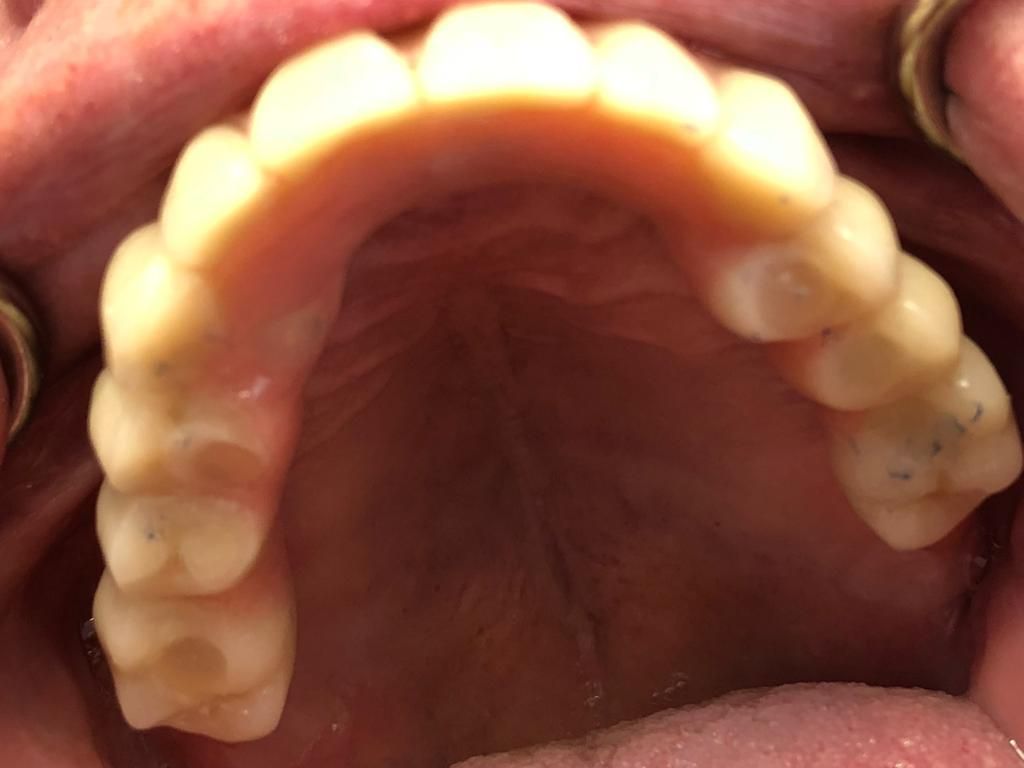

Presso lo Studio Dentistico del Dr. Cerquaglia Stefano a Terni, l'implantologia dentale rappresenta una soluzione all'avanguardia per ripristinare la funzionalità e l'estetica del sorriso dei nostri pazienti. Gli impianti dentali, costituiti da radici artificiali in titanio, vengono inseriti nell'osso mascellare o mandibolare per sostituire uno o più denti mancanti.

Questo approccio offre numerosi vantaggi: una stabilità e una durata eccezionali, un aspetto naturale che si integra perfettamente con il resto della dentatura, e la prevenzione della perdita ossea, spesso associata alla mancanza di denti.